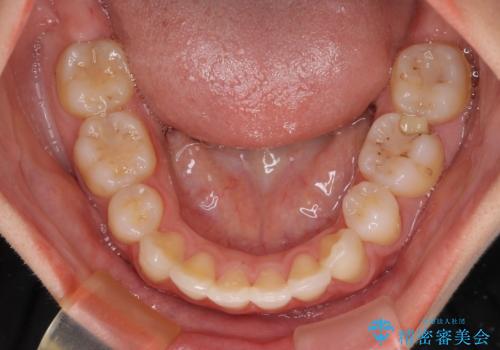

- 矯正装置

- ハーフリンガル

- 口元の突出感を気にして来院された患者様です。

上下左右の第一小臼歯4本を抜歯して口元を下げる治療計画としました。

目立たない装置が希望であったため、上顎が裏側装置である、ハーフリンガル装置を選択されました。

3年半ほどで終わる予定でしたが、途中引っ越し、出産、引っ越し、出産を繰り返し、なかなか来院することができず、装置を外すまでに8年以上の期間がかかってしまいました。